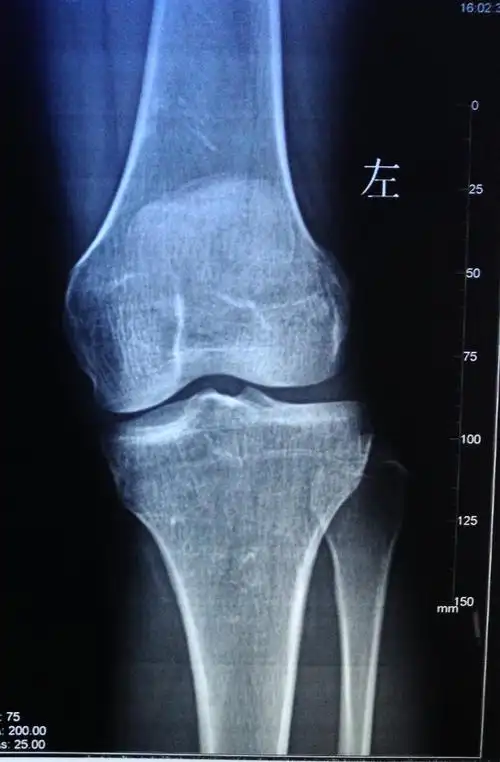

一月前左膝关节弯曲会痛长时间不动要活动一段时间